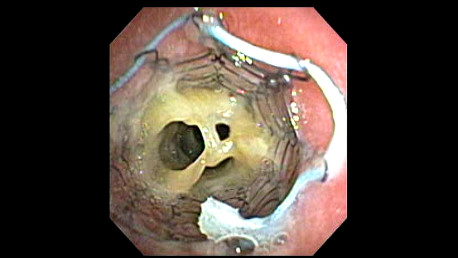

Post tracheobronchoplasty bronchoscopy. Because the mesh was not integrating into the trachealis muscle as it should, they placed a metal stent (usually not used for something like this) to try press the trachealis into the mesh as it would heal. I was on multiple mucus reduction agesnt at the time, as well.